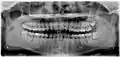

Дистоугольно ретинированы верхний левый (изображение справа) и верхний правый (изображение слева) зубы мудрости. Левый нижний зуб мудрости ретинирован горизонтально. Нижний правый зуб мудрости вертикально ретинирован.